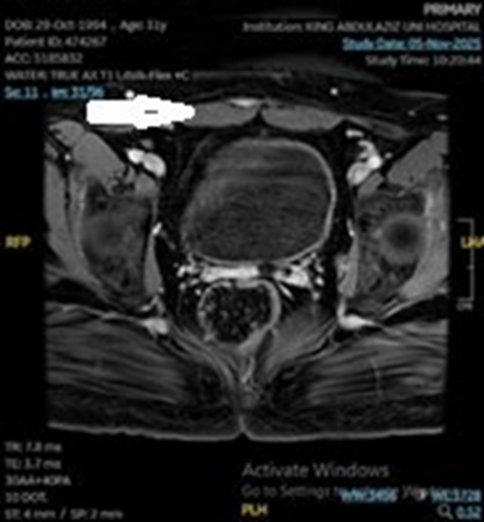

Post-therapy imaging after four cycles demonstrated a mixed response: a stable/enlarged left pelvic sidewall node persisted, while a metastatic right rectus muscle lesion regressed, and pulmonary nodules remained stable without new lesions (Figure 3). The current plan is to continue chemotherapy with immunotherapy and to repeat imaging after three additional cycles to guide decisions about local control strategies (radiation or possible surgical debulking). Throughout, the patient’s tolerability of therapy has been monitored, with emphasis on balancing efficacy against treatment-related morbidity in the context of obesity and diabetes. Ongoing multidisciplinary follow-up and serial imaging remain essential to assess response and refine the treatment plan.

Figure 3: Axial post-contrast T1 MRI showing marked reduction in the left rectus muscle lesion, indicating good response to chemotherapy.